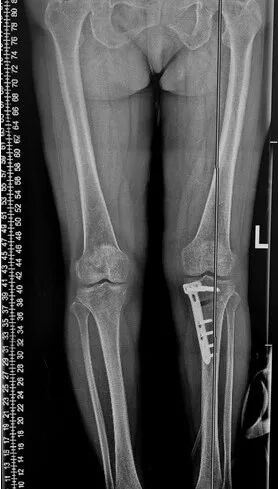

患者酷爱运动,因“O型腿”,膝关节内侧疼痛难忍就诊,新院区骨科关节组医师团队深入践行个性化治疗理念:每位患者的年龄、职业、活动需求、病变程度都独一无二,要为其“量体裁衣”,制定最佳方案。经过细致的影像学评估和数据分析,团队发现该患者病变仅局限于膝关节内侧间室,外侧软骨和韧带功能良好,完全符合HTO手术的“精准适应证”。术前,团队利用数字化技术进行了精确的截骨模拟和力线规划,确保了手术方案的“毫米级”精准度。

手术中,关节组医师团队凭借精湛技艺,犹如一位“骨骼工程师”,精确地调整了患者的下肢力线,将压力从磨损的内侧成功转移至健康的外侧。术后患者膝关节疼痛症状迅速缓解,并于次日开启康复训练,重燃运动希望。